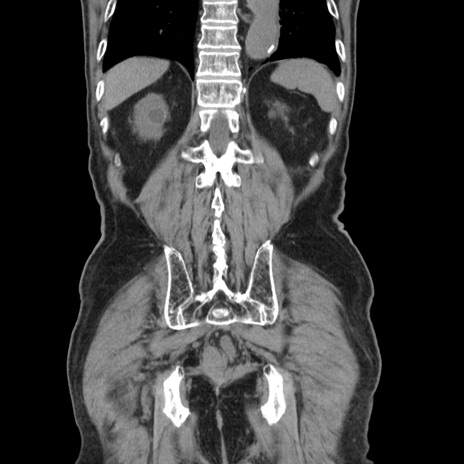

症例24(冠状断像)

【症例】80歳代男性

【主訴】左側腹部痛、嘔吐

【現病歴】本日早朝より左腹部に痛みあり。昼頃嘔吐認めたため、救急要請。

【既往歴】直腸癌(Mile手術)、胆摘

【身体所見】意識清明、BT 35.9℃、BP 221/93mmHg、SpO2 97%(RA) 、腹部:左ストーマ周囲に限局性の腹部膨隆あり。 膨隆部自発痛・圧痛あり・軟。

【データ】WBC 7700、CRP 0.09